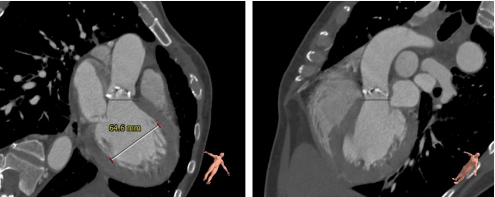

CT影像筛查

瓣环平面测量

找到窦底(二叶瓣 )

确定瓣环平面周长79.9mm

直径25.4mm

确认冠脉风险,左右冠高度尚可,冠脉平面

窦部大小

左室流出道:

Min: 22.7mm

Max: 32.9 mm

Average: 27.8 mm

心室大小

STJ

升主动脉